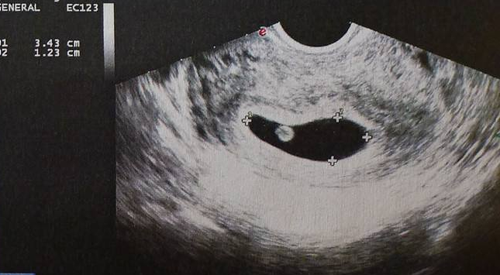

我是第一次怀孕,还是个新妈妈呢,不大知道怀孕后会有怎样的改变,但刚怀孕,心理特别想知道怀孕后宝宝到底长了没,有多大了,虽然现在胎宝宝还只是一个小小的孕囊,但也很好奇两个月孕囊到底有多大,怀孕两个月孕囊值在多大是正常的呢?

怀孕两个月孕囊大小多少正常

孕囊大约在4厘米左右。

一般女性在怀孕的2个月左右,其孕囊大小可以在4厘米,胎芽一般是2厘米左右,但是这只是个参考值,孕妇孕囊的大小和受孕早晚以及孕妇营养、基因等都有直接的关系。

怀孕两个月如何根据孕囊算孕周

孕囊三个数据公式:孕囊的大小(长+宽+高)/3+30,单位mm,结果为天数。胎芽是胎芽长+6.5,单位cm,为周数。

例如:孕囊大小为:2.4*1.1*0.8,则计算结果为:(2.4+1.1+0.8)/3+30=32天